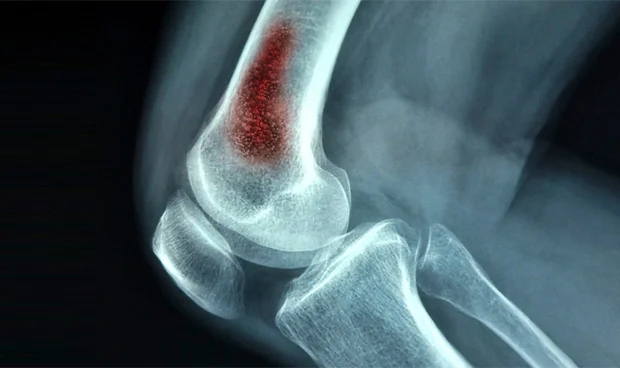

El término «osteomielitis» se refiere a la inflamación del hueso, que puede resultar de etiologías tanto infecciosas como no infecciosas. Una etiología no infecciosa particularmente importante de la osteomielitis que puede simular una infección es la osteomielitis crónica no bacteriana, que también se conoce como osteomielitis crónica multifocal recurrente. Esta es una enfermedad autoinflamatoria que desencadena lesiones óseas estériles que pueden afectar uno o más lugares del esqueleto, y la presentación clínica puede ser sorprendentemente similar a la de la osteomielitis infecciosa.